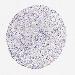

KIDNEY RENAL CLEAR CELL CARCINOMA (VALIDATION) - Interactive survival scatter ploti

The Survival Scatter plot shows the clinical status (i.e. dead or alive) for all individuals in the patient cohort, based on the same data that underlies the corresponding Kaplan-Meier plots. Patients that are alive at last time for follow-up are shown in blue and patients who have died during the study are shown in red.

The x-axis shows the expression levels (FPKM) of the investigated gene in the tumor tissue at the time of diagnosis. The y-axis shows the follow-up time after diagnosis (years). Both axes are complimented with kernel density curves demonstrating the data density over the axes. The top density plot shows the expression levels (FPKM) distribution among dead (red) and alive patients (blue). The right density plot shows the data density of the survived years of dead patients with high and low expression levels respectively, stratified using the cutoff indicated by the vertical dashed line through the Survival Scatter plot. This cutoff is automatically defined based on the FPKM cutoff that minimizes the p-score. The cutoff can be changed by dragging the vertical line or by entering a cutoff value in the square labeled "Current cut-off".

Under the Survival Scatter plot the p-score landscape (black curve; left axis) is shown together with dead median separation (red curve; right axis). Dead median separation is the difference in median mRNA expression between patients who have died with high and low expression, respectively. It is calculated as follows: median FPKM expression of dead patients with high expression - median FPKM expression of dead patients with low expression. This is intended to aid the user in visually exploring custom cutoffs and the associated p-scores and dead median separation.

Individual patient data is displayed and can be filtered by clicking on one or more of the category buttons on the top of the page. Categories describing expression level and patient information include: high, low, alive, dead, female, male and tumor stages. The scale of the x-axis can be toggled between linear and log-scale by clicking on the "x log" button. Mouse-over function shows TCGA ID, patient information and mRNA expression (FPKM) for each patient.

& Survival analysisi

Kaplan-Meier plots summarize results from analysis of correlation between mRNA expression level and patient survival. Patients were divided based on level of expression into one of the two groups "low" (under cut off) or "high" (over cut off). X-axis shows time for survival (years) and y-axis shows the probability of survival, where 1.0 corresponds to 100 percent.

MYO5A is not prognostic in Kidney Renal Clear Cell Carcinoma (validation)

: 9.49

Average pTPM 11.8

Number of samples 100